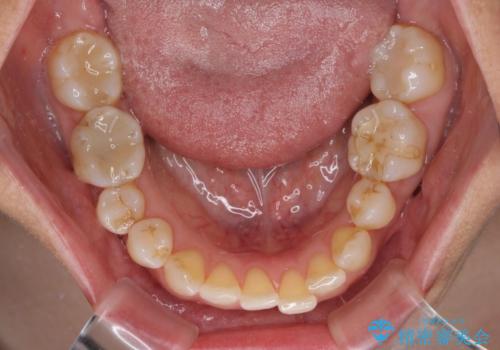

- 骨格的な咬み合わせのズレ、前歯のデコボコとクロスバイトを気にして来院された患者様です。

奥歯の噛みにくさが顕著なためマウスピースではなく、ワイヤー装置による矯正治療を行うこととしました。

下顎の正中を歯1本分ずらした位置とすることで、外見上の骨格的なずれをカバーするように計画しました。

クロスバイトを改善したことで、前歯の負担が軽減し、安定して噛めるようになりました。